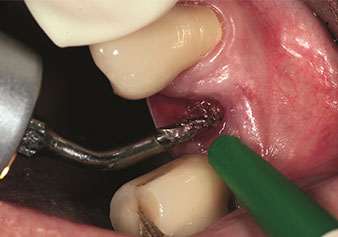

Endikasyon, dahili sinüs lifti

W&H ayrıca iç sinüs lifti için mükemmel bir çözüm sunar. Uygun aletlerle maksiller sinüs hazırlığından sonra

(Şekil 3), yeni uç Z35P (Şekil 4) ile membran hidrodinamik olarak kaldırılır. Aynı uç seti ayrıca Piezo cerrahisi yöntemiyle, artan çaplardaki implant yeri hazırlığı için de kullanılabilir [şekil 3 ve 4, Dr. Mario Kirste’nin (Frankfurt/Oder) onayı ile kullanılmıştır].